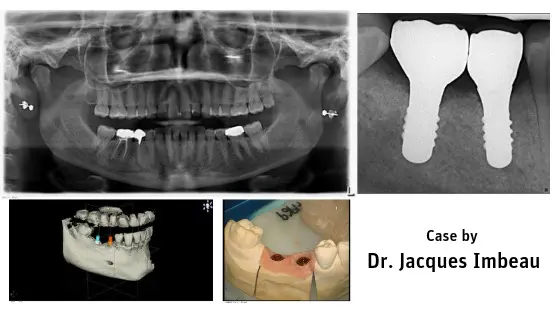

Posterior Zirconia Implants Guided Surgery

Social Media Case Report posted on Facebook by Dr. Luis Alicea – Your Desired Smile – Posterior ZERAMEX Zirconia Implants Guided Surgery